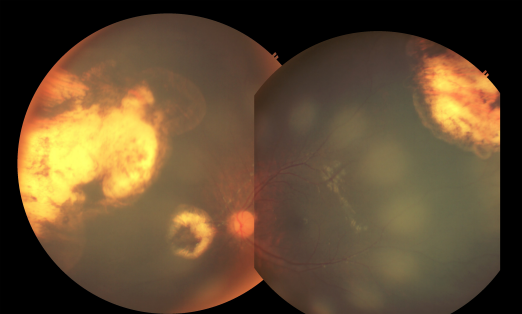

Recurrent vitreous seeds overlying the tumor at the superotemporal mid periphery and at the inferior periphery were clinically undetectable (regression type 0) after 2 cycles of intravitreal melphalan injection (Figure 2 [Fig. 2]). There were no new tumors and vitreous seeding observed on the left eye 6 months from the last intravitreal injection of melphalan. There were no documented complications of intravitreal melphalan injection.

Figure 2: Fundus photo montage showing clinically undetectable (regression type 0) vitreous seeds 6 months after 2 cycles of intravitreal melphalan injection